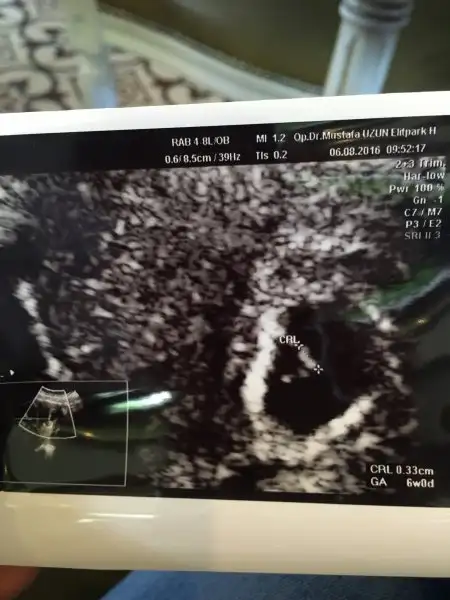

Kızlar kesemizi gördük kalp atışı da başlamış haftaya duyarız dedi doktorumuz :) Darısı başınızaCanim sagol şimdilik iyi gidiyor.simarik83 dün kontrole gidecekti keseyi görmüştür insallah. Ben cuma gününe randevu aldım. Umarim güzel haberler alırım. Sen de insallah bir an önce mutlu sona ulaşırsın hayırlı haberlerini bekliyorum

Canim çok güzel. Tebrik ederim hep böyle güzel fotolarini görürüz inşallah. Çok mutlu oldum senin adına. Gozunaydin . Ben de aslında cuma gidicem ama yarinda riskli gebelik uzmanına gidicem. Bakalım neler söyleyecek merak içerisindeyim. Dualarinizi esirgemeyinKızlar kesemizi gördük kalp atışı da başlamış haftaya duyarız dedi doktorumuz :) Darısı başınıza

Tebrik ederim canım. Hep böyle sağlıkla devam eder inşallah. Ne büyük mutluluk. MaşallahKızlar kesemizi gördük kalp atışı da başlamış haftaya duyarız dedi doktorumuz :) Darısı başınıza